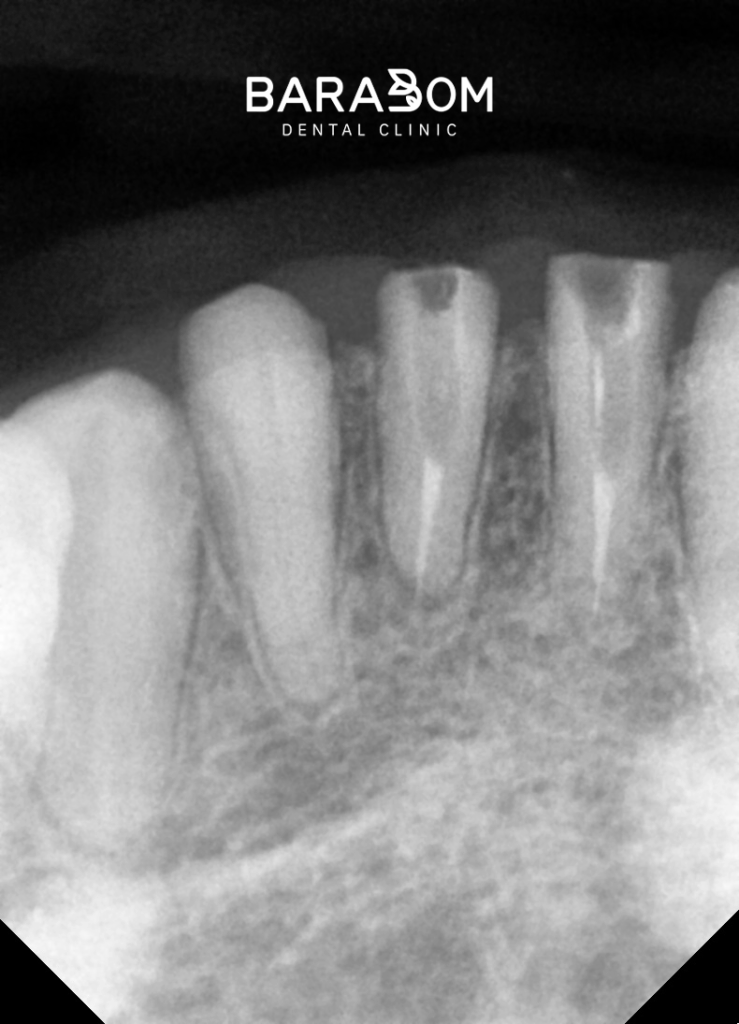

대개 교모로 인하여 수직 고경이 상실된 케이스를 보면 치관의 길이가 매우 짧습니다. 이런 상태에서 크라운을 씌우게 되면 당연히 안정을 얻기 어렵습니다.

그럼 자주 보철이 탈락하게 되어 불편으로 이어질 수 밖에 없는데, 현재 하악 앞니 뿐만 아니라 어금니도 치아 머리의 길이가 짧은 상태였습니다. 하악 절치부 치관 길이가 매우 짧으며, 상악 절치 구개부와 간격이 불과 2mm 이내였습니다. 현재 상태로써 새로운 보철을 제작하긴 어렵다 판단되고 있습니다.

앞서 설명드린 것처럼 교합고경을 재건할 때, 여러 사항을 고려하여 신중을 기여해야 됩니다. 하악 구치부 크라운 수복을 진행한 결과, 앞니쪽에 3mm 가량의 공간이 형성되었습니다.

보철이 올라갈 여유가 확보되긴 했으나 그 정도가 충분한 건 아니라 골 삭제를 동반한 치관연장술을 함께 진행하는 방향을 택해볼 수 있습니다. 말 그대로 잇몸뼈를 어느 정도 삭제해줌으로써 치아 머리의 길이를 늘려주는 술식을 말합니다.

골 삭제와 더불어 포스트를 세워줌으로써 충분한 강도를 되찾아줌과 동시에 코어를 수복하여 길이를 확보하여 지대치 형성이 마무리되었습니다.